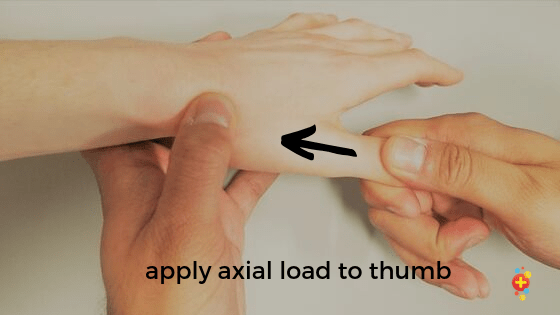

(3) 엄지손가락 압박검사(Pain with longitudinal compression of thumb)

-

- 엄지손가락뼈를 축으로해서 손목쪽으로 압력을 가할 때 통증유발을 확인합니다.